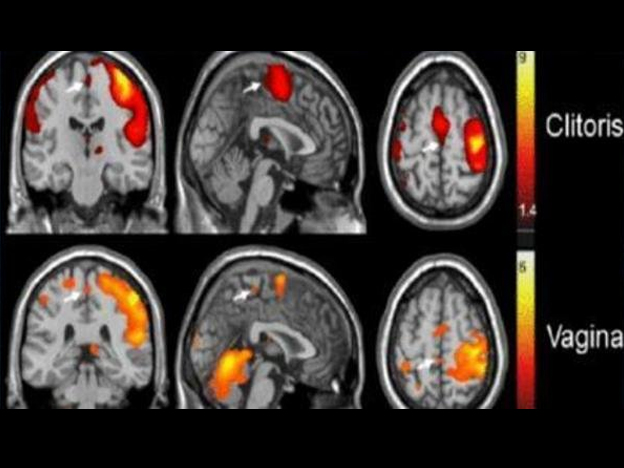

En la Universidad de Rutgers detectaron cuáles

son las zonas del cerebro que se activan con el clímax.

Por primera vez un grupo de científicos trazó "el mapa del

placer" en el cerebro femenino gracias al estudio de los orgasmos de

un grupo de mujeres en un laboratorio de la estadounidense

Universidad de Rutgers.

Descubrir qué parte del cerebro se activa cuando una mujer tiene

un orgasmo fue el objetivo de un neurólogo americano Barry Komisaruk.

Para averiguarlo sometió a decenas de mujeres a una prueba en un

escáner y les hizo una resonancia magnética en plena excitación

sexual. Las manchas rojas son las partes del cerebro que se activan

cuando se estimula el clítoris o la vagina. Cada uno manda

información a un sitio distinto del cerebro.